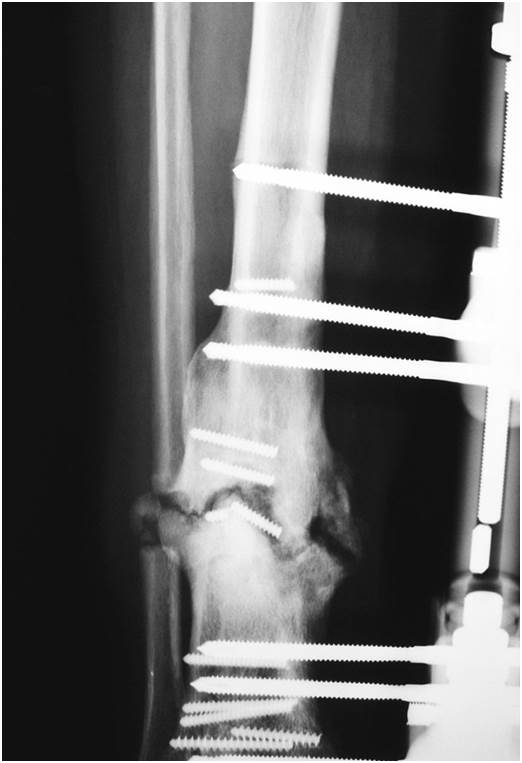

De las fracturas distales de tibia 15 se produjeron como resultado de caídas de baja energía y una se produjo de manera espontánea. Paciente de 30 años de edad con fracturas en tibia y peroné derechos después de caída desde una altura elevada. Así como otras roturas de hueso estas también son de carácter delicado pudiendo presentar complicaciones graves.

Paciente de 30 años de edad con fracturas en tibia y peroné derechos después de caída desde una altura elevada. Chica de 18 años es aficionada a la escalada. Aquí te dejo una que te recomiendo. Sintomatología Violencia del trauma Compromiso de partes blandas Desplazamiento Dolor Impotencia funcional. Después de 5 meses y una semana de la operación llego de la rehabilitación y como siempre es el momento que mejor me encuentro de todo el día pruebo de cam. Volver a correr tras una fractura de peroné. Y si tienes la tibia el peroné o el fémur fracturado la media debe llegarte hasta la ingle. Tras un fallo técnico en las cuerdas de seguridad calló al vacío perpendicularmente al suelo desde tres metros de altura el impacto provocó la fractura distal del peroné y la tibia. Las lesiones graves se producen debido a accidentes de tránsito accidentes en el deporte o caídas y pueden provocar una fractura con desplazamiento de tibia y peroné en la región de la articulación del tobillo.